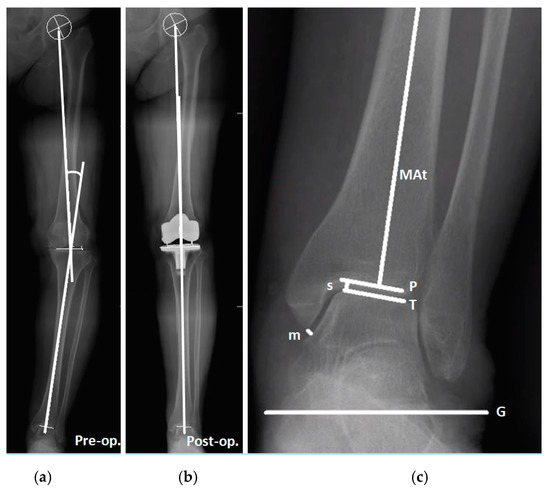

2.2. Study Grouping and Parameters of Knee and Ankle

2.3. Radiographic Measurements